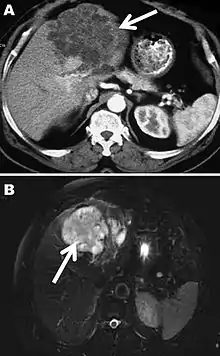

The diagnosis of polycystic echinococcosis involves isolating the protoscoleces during surgery or after the patients death in order to identify E. vogeli. Imaging, such as ultrasound and CT scans, can also be used to identify polystytic structures, but this method is not preferred as images are similar to other types of echinococcosis and liver cancer. New studies show that PCR may identify E. vogeli in the patients tissues.[5]

Polycystic echinococcosis (PE) is an extremely lethal helminthic disease in humans, which is caused by the larval form of E. vogeli. Type I PE consists of polycystic masses in the liver and abdominal cavity. Type II also has polcystic masses in the liver and abdominal cavity, but includes hepatic insufficiency. Type III has polcystic masses in the liver and chest cavity. In type IV polycystic masses occur only in the mesenteries. Type V has calcified cysts in the liver and lung.[4] Type II seems to have the highest mortality rate due to the complications involved with hepatic insufficiency. Due to the similarities between liver cancer and polycystic echinococcosis, PE is hard to diagnose and could deadly when metastasized to other organs.